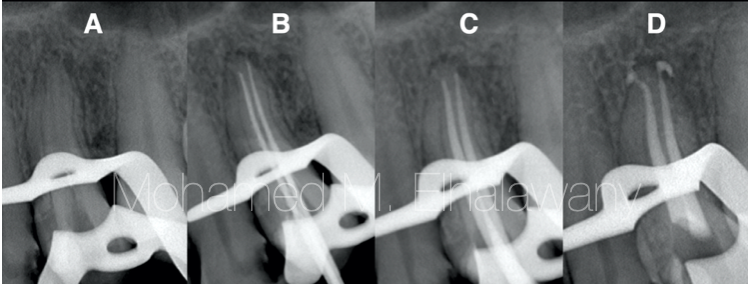

图4

虽然这个囊肿仅通过手术切除即可治疗,但有一颗长时间开放根管的牙齿需要在进行任何手术干预之前进行彻底的清洁和成形,然后进行充填。

该案例的挑战之一是去除前磨牙根管内的未知物质,该物质闻起来类似于甲醛。但由于良好的冲洗方案和超声波激活,成功地完全去除了该物质(图4A),然后进行了根管治疗的所有步骤,并通过X光确认了每一个步骤。牙齿使用基于MTA的封闭剂和连续波凝结技术进行充填(图4D)。